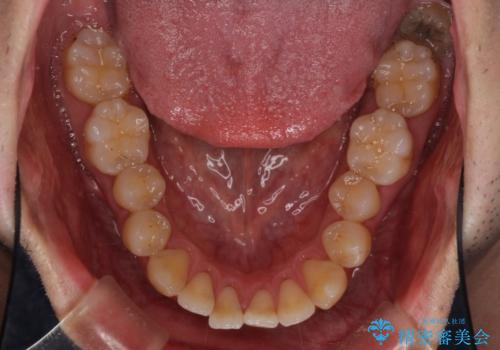

- 上下の前歯の反対咬合を気にして来院された患者様です。

インビザラインを用い、下顎はIPR(歯と歯の間を削る)と歯列全体を後方に移動させ、上顎は前歯を持ち上げることで、反対咬合を改善していくこととしました。

八重歯の歯根が見えている点も気になっているので、矯正歯科治療後に歯肉移植による根面被覆を行うこととしました。